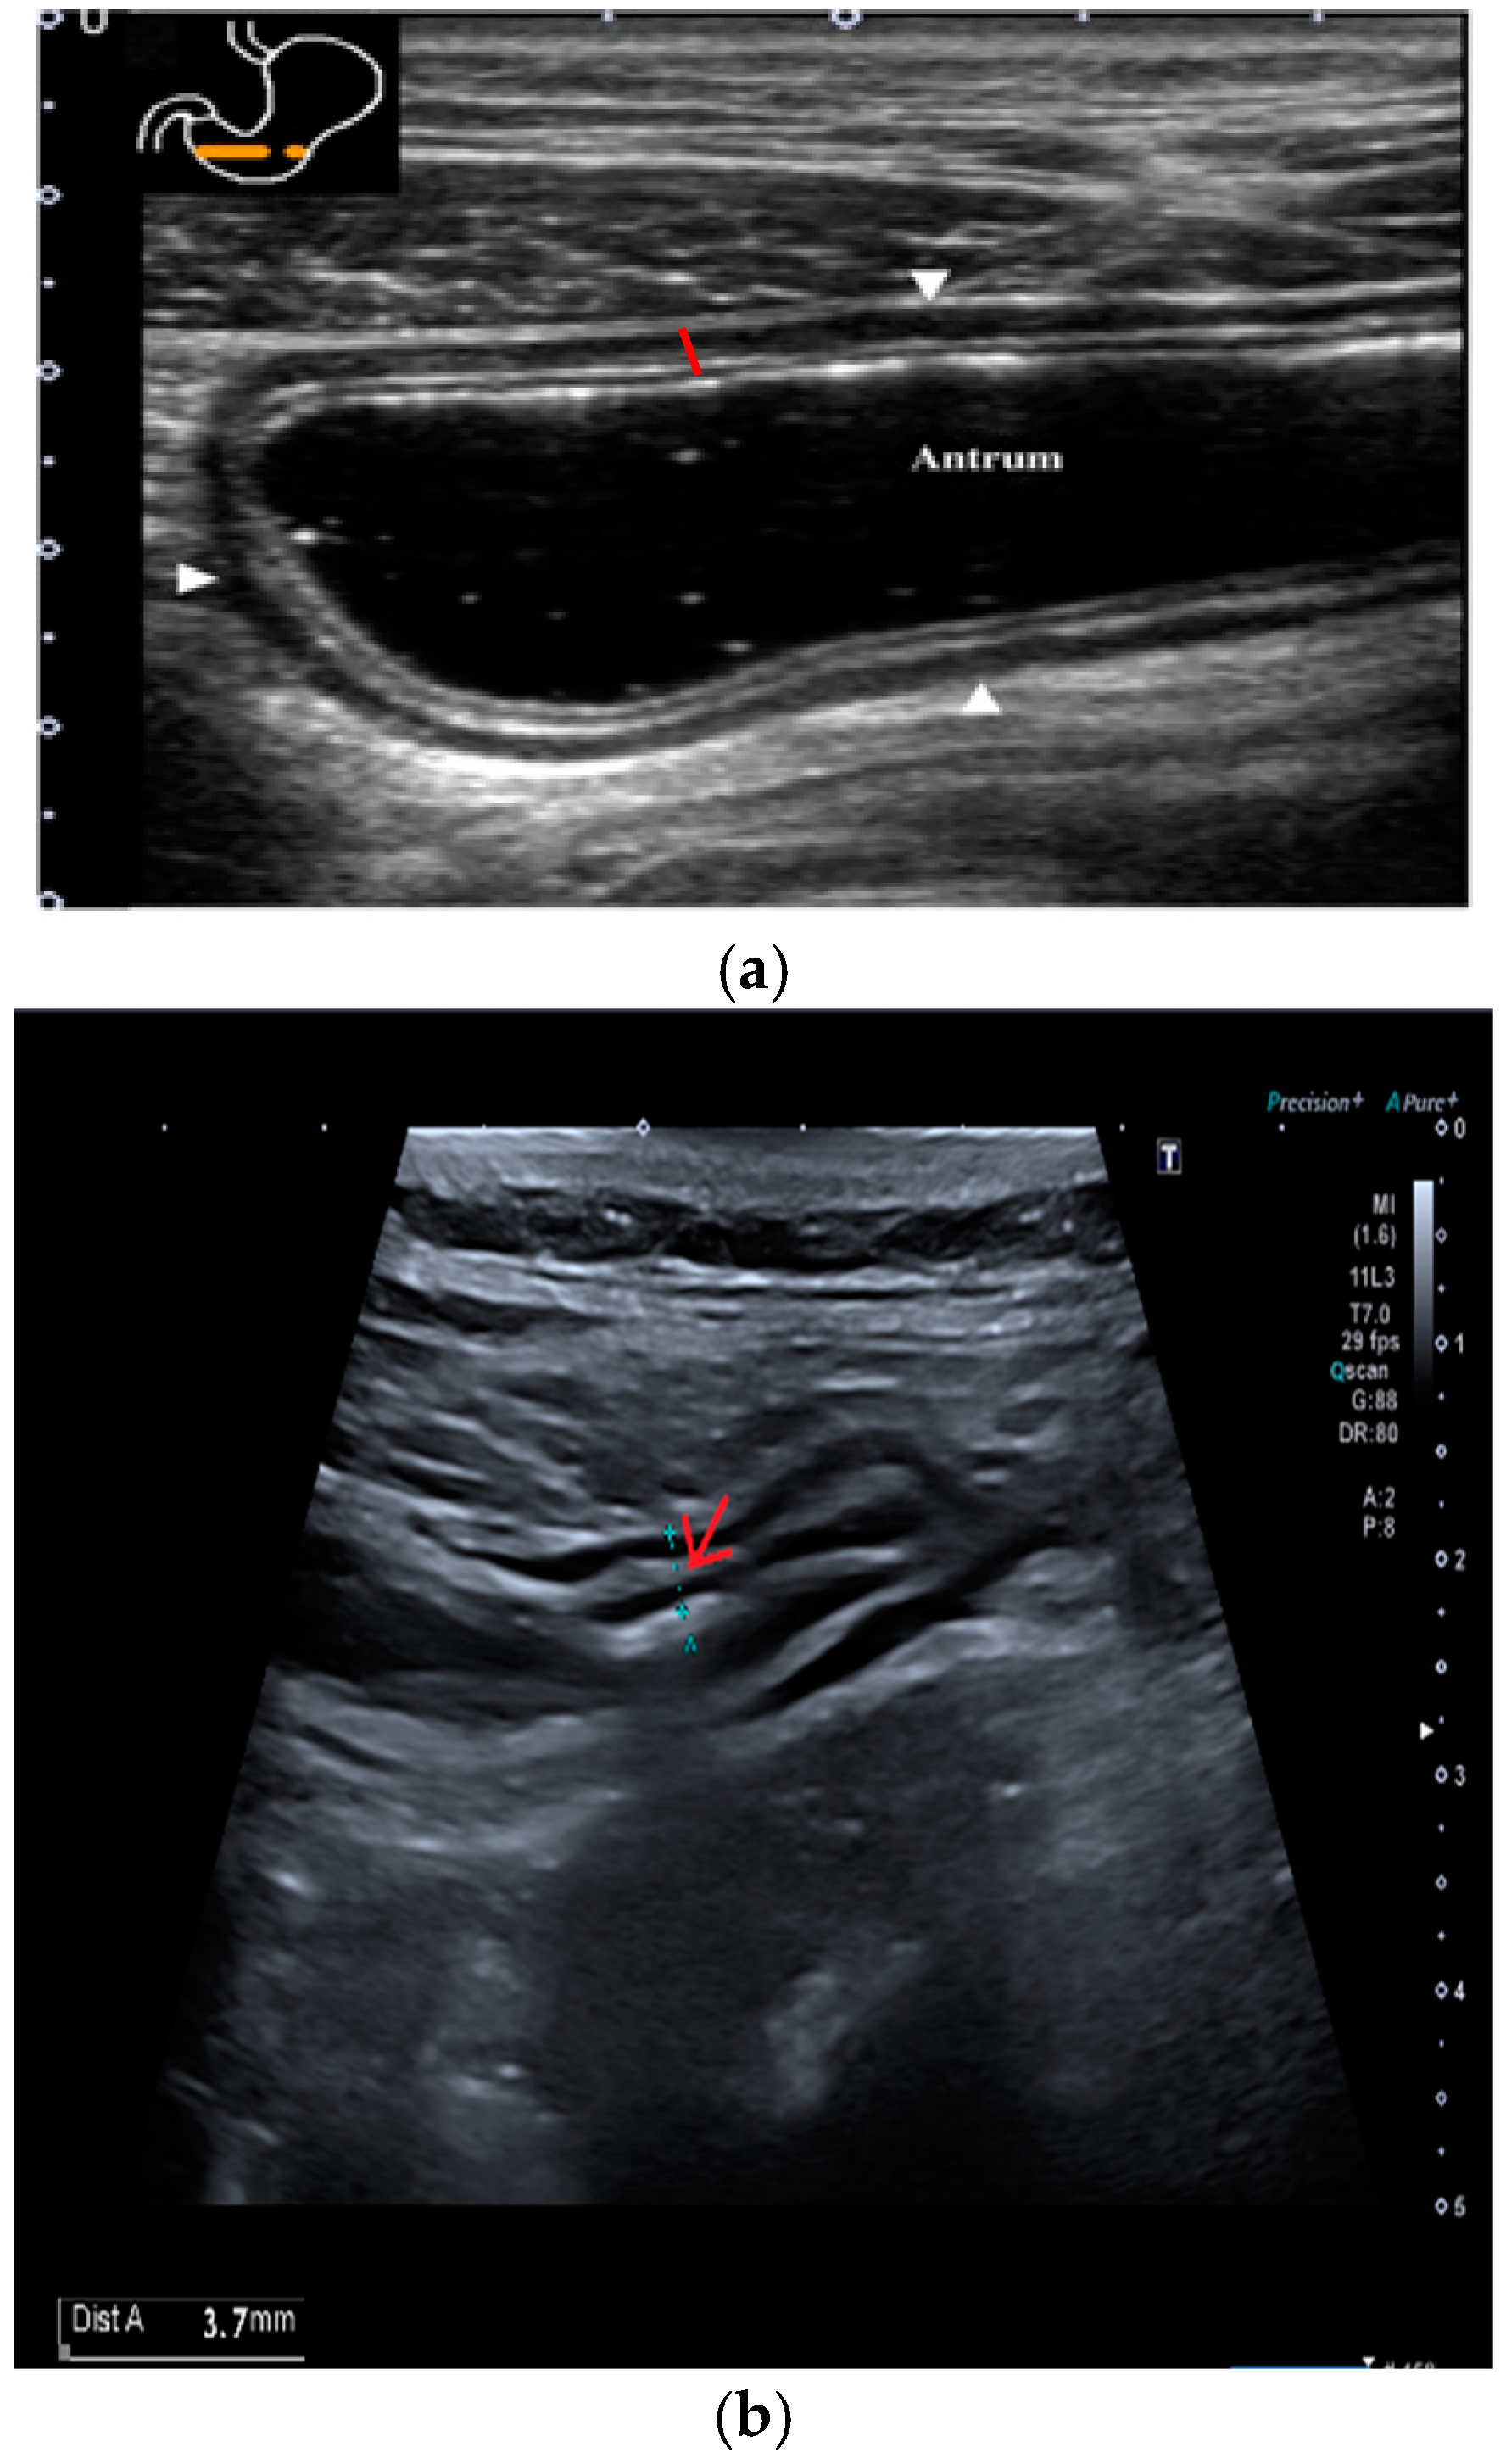

The submucosal thickness and reduced motility were significantly higher in the group of patients with histological confirmation of Helicobacter pylori-related gastritis (p < 0.001) (Figure 1 and Figure 2a,b).

Figure 2. Transversal section of gastric antrum with different layers of the wall. The red line represents the anterior wall of the antrum, showing the normal alternation of layers. Starting from inside: lumen–mucosa interface, mucosa, submucosa, muscularis, and serosa. (a) Antrum in a patient without Hp-related gastritis, with a normal submucosal layer. (b) Antrum in a patient with Hp-related gastritis, showing a thickened submucosa, marked by a red arrow.